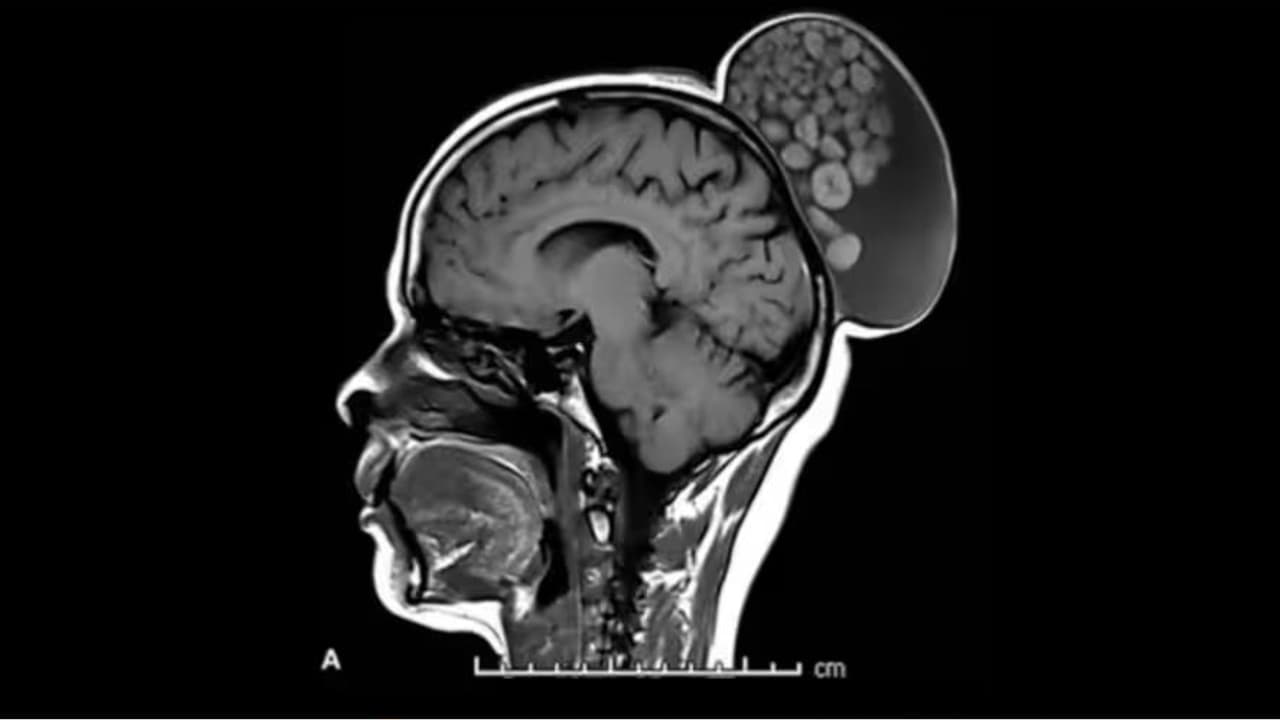

बेंगलुरु में डॉक्टरों ने हाल ही में एक महिला का अनोखा ऑपरेशन किया है। जिसके सिर पर कंचे की बोरी जैसी उभरी हुई गांठ थी। श्रीसत्य साईं इंस्टीट्यूट ऑफ हायर मेडिकल साइंसेज ने रेडियोलॉजी पत्रिका में इस असामान्य ऑपरेशन के बारे में विस्तार से जानकारी दी है। 52 वर्षीय महिला बचपन से ही सिर पर सूजन के साथ जी रही थी लेकिन अब तक उसने कभी इसकी जांच भी नहीं कराई थी। इस सूजन में दर्द नहीं होता था और यह करीब 6 इंच लंबी, 4 इंच चौड़ी थी।

एमआरआई स्कैन से मिली डॉक्टरों की इसकी जानकारी

डॉक्टर्स ने जब इसकी जांच की तो एमआरआई स्कैन से पता चला कि यह गांठ उसके सिर के पीछे मांसल भाग में बालों के जूड़े जैसा बन गया था। इसको हटाने के लिए की गई सर्जरी के दौरान डॉक्टरों ने पाया कि यह तरल पदार्थ, बाल, वसायुक्त अणुओं और मोटे बाहरी किनारों के साथ केराटिन की बॉल्स से भरा हुआ था, जो अलग-अलग आकार के थे। जानकारी के लिए बता दें कि केराटिन एक तरह का प्रोटीन होता है जो बालों, नाखूनों और स्किन की बाहरी पर्त का आधार बनता है। महिला में मिले इस चीज को डर्मोइट सिस्ट कहते हैं। यह भ्रूण कोशिकाओं से ही बनते हैं और यह बाल, दांत या तंत्रिकाएं बना सकते हैं। ये अक्सर सिर और गर्दन में दिखते हैं। यह अंडाशय और शरीर के ऊपरी हिस्से में भी पाया जाता है।